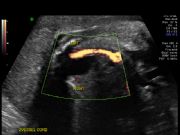

Color flow Doppler of fetal

heart to show cross over of

Left Ventricular Outflow Tract

(LVOT) and Right Ventricular

Outflow Tract (RVOT)